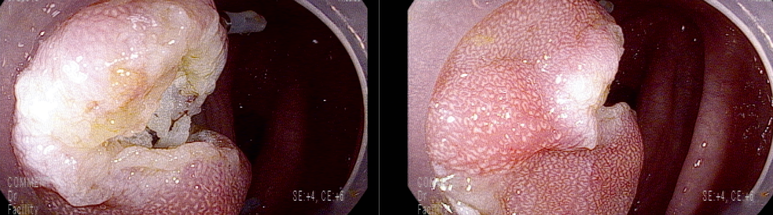

19-20 mm 크기의 유경성(목이있는) 용종은 클립을 적절히 사용하여 출혈예방함

마지막 유경성 거대 용종을 제외하고 점막 소구 패턴(pit pattern)이 불규칙하게 관찰되어(Vi) 고등급의 선종 혹은 점막암을 의심하여 충분히 융기시켜 경계가 확실히 포함되고 한조각으로 완전 절제하기 위해 넓게 절제함